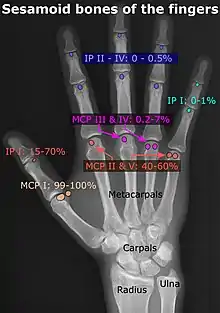

Wrist and hand

| Accessory bone | Prevalence on the right (R) and left (L)[5] |

|---|---|

| Os ulnostyloideum | 1.5% R, 2.4% L |

| Os centrale | 1.3% R, 2.1% L |

| Os trapezium secundarium | 0.5% R, 2.1% L |

| Os styloideum | 1.2% R, 1.2% L |

| Os radiale externum | 1% R, 0.9% L |

| Os triangulare | 1% R, 0.9% L |

| Os paratrapezium | 0.3% R, 0.9% L |

| Os capitatum secundarium | 0.8% R, 0.3% L |

| Os Hypotriquetrum | 0.5% R |

| Os hypolunatum | 0.3% L |

| Os epilunatum | 0.3% R, 0.3% L |

| Os ulnare externum | 0.3% L |

| Os pisiforme secundarium | 0.3% R |

| Os epitrapezium | 0.3% L |

| Os vesalianum manus | 0.3% L |